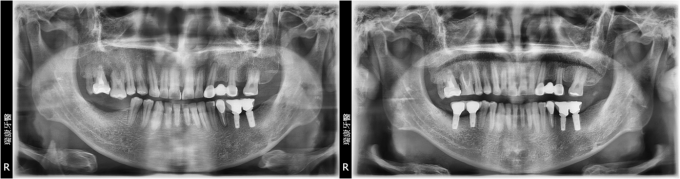

上顎多顆缺牙重建

病患蘇小姐,65年次,上班族

主訴 : 想要重建右上缺牙區

治療計劃 : 安排精密3D電腦斷層評估後,進行人工植牙, 三個月後進行APF增加角化黏膜 後續接出假牙基座印模製作正式假牙!

PS:患者表示:醫師很細心,解說詳細!

實例照片僅為資訊介紹及分享,效果可能因個人體質及保養方式不同而有所差異。